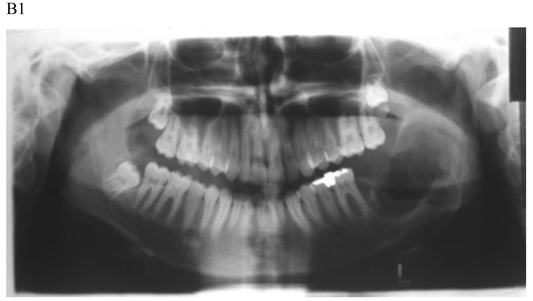

The treatment objective is restoring the morphology and function of the affected area. There are two basic surgical procedures, namely marsupialization (decompression) (Fig.1) and enucleation. Marsupialization, a relatively simple procedure, consists of surgically producing a “window” in the cystic wall to relieve intra-cystic tension. After this, the cystic cavity slowly decreases in size. The cavity is lightly packed with paraffin gauze until the line of junction between the cystic lining and the oral mucosa has healed. Three to six months later, enucleation is performed [16].

Figure 1

Dentigerous cyst affecting the left mandible of a 15-year-old boy treated by marsupiallization. At presentation, there was an acute infection in the area. A) Pre-operative radiographs: 1) Panoramic radiograph demonstrating a tooth within a large radiolucent area in the left mandible; 2) Axial CT scan demonstrating expansion of the body of the left mandible with very thin buccal and lingual cortices. A tooth is within the lumen; 3) Coronal CT of the mandible demonstrates an expansion of the ascending ramus of the left mandible with very thin cortical borders. A tooth is within the lumen. B. Postoperative radiographs: 1) Panoramic radiograph shortly post-marsupialization, extraction of tooth 37 that was adjacent the cyst as well as tooth 38 that was within the cyst; 2) Panoramic radiograph one year post-treatment. The radiodensity of the cystic area is similar to normal bone, indicating complete bone regeneration.

The notable disadvantages of the technique are: (a) it is a two-stage surgical procedure, (b) pathological tissue is left behind and a more sinister pathological process (i.e., squamous cell carcinoma) may be overlooked [21], and (c) in a large cystic cavity it takes a long period of time for the bone to regenerate.

Enucleation with primary closure is the treatment of choice [22]. It is a one-stage surgical treatment followed by periodic radiographic examinations at regular intervals to observe the progress of bone regeneration of the defect. It also allows pathologic examination of the entire specimen for histopathologic diagnosis. Enucleation can be done only when the jaw bone adjacent to the cyst is intact. If CT demonstrates erosions in the buccal or lingual cortices, marsupialization should be the treatment of choice (Fig. 1) [4].